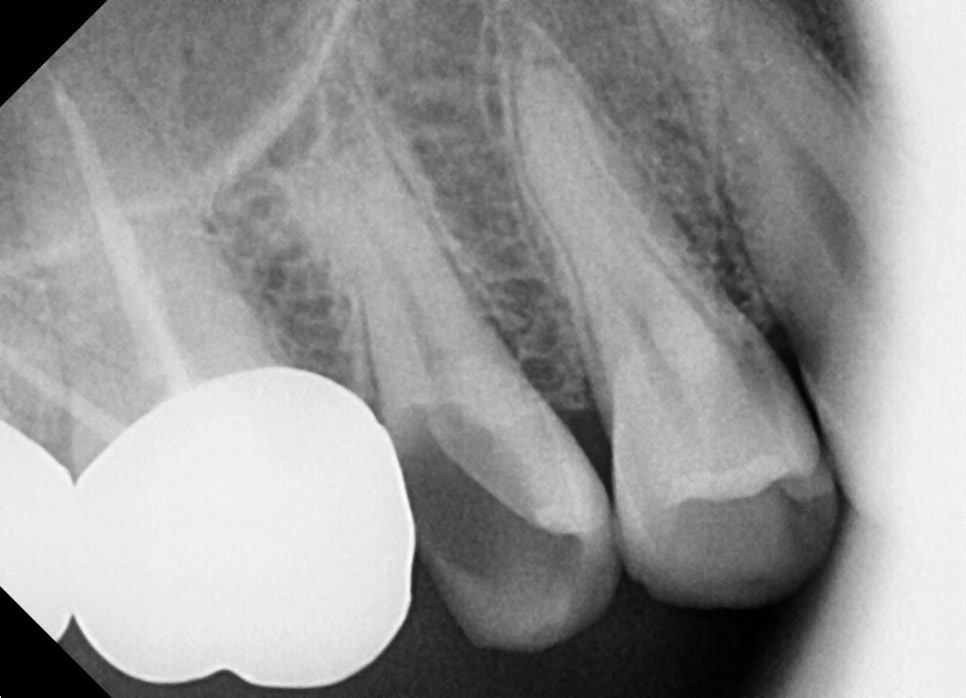

엑스레이를 확인해보니 충치가 너무 심해 치아가

깨진 상태로 오셨어요.

이렇게 어금니까 깨졌을 때에는

신경치료가 꼭 필요합니다.